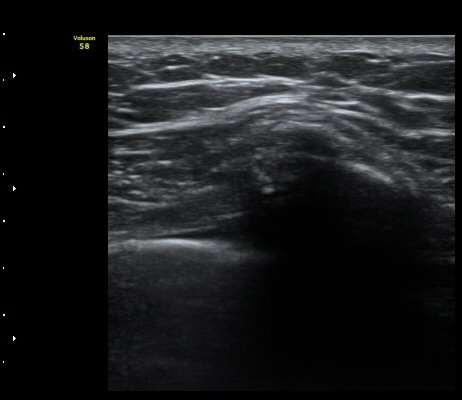

ÃÊÀ½ÆÄ °Ë»ç

¹Ì¼¼ÇÏ°Ô °¥ºñ»À ÇÇÁú°ñ ¿¬°á¼º ¼Ò½Ç°ú ¿¬ºÎÁ¶Á÷ ºÎÁ¾ÀÌ °üÂûµÊ(loss of cortical continuity and soft tissue swellingof rib)   »çÁø 1, 2, 3

3, 4,, 5 ¹øÂ° °¥ºñ»À °ñÀýÀÌ È®ÀεÊ.